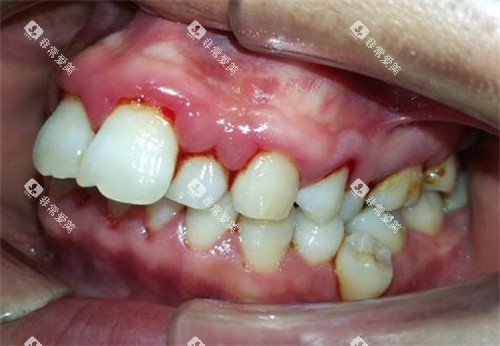

牙齿不整齐不仅影响面部美观,还可能导致口腔清洁困难,增加龋齿和牙周疾病的发生风险。

牙齿矫正可以有效改善牙齿排列问题,提升口腔健康和美观度。

美冠塔口腔的牙齿矫正方式主要有传统金属矫正、陶瓷矫正、隐形矫正等。

传统金属矫正价格相对较为亲民,一般在 8000 - 15000 元左右。

陶瓷矫正由于其美观性较好,价格会稍高一些,大约在 12000 - 20000 元。

隐形矫正则具有美观、舒适、可摘戴等优点,价格相对较高,通常在 25000 - 40000 元之间。

除了矫正方式,患者的牙齿矫正难度也是影响价格的重要因素。

如果患者的牙齿畸形程度较为重的,矫正周期会相对较长,费用也会相应增加。